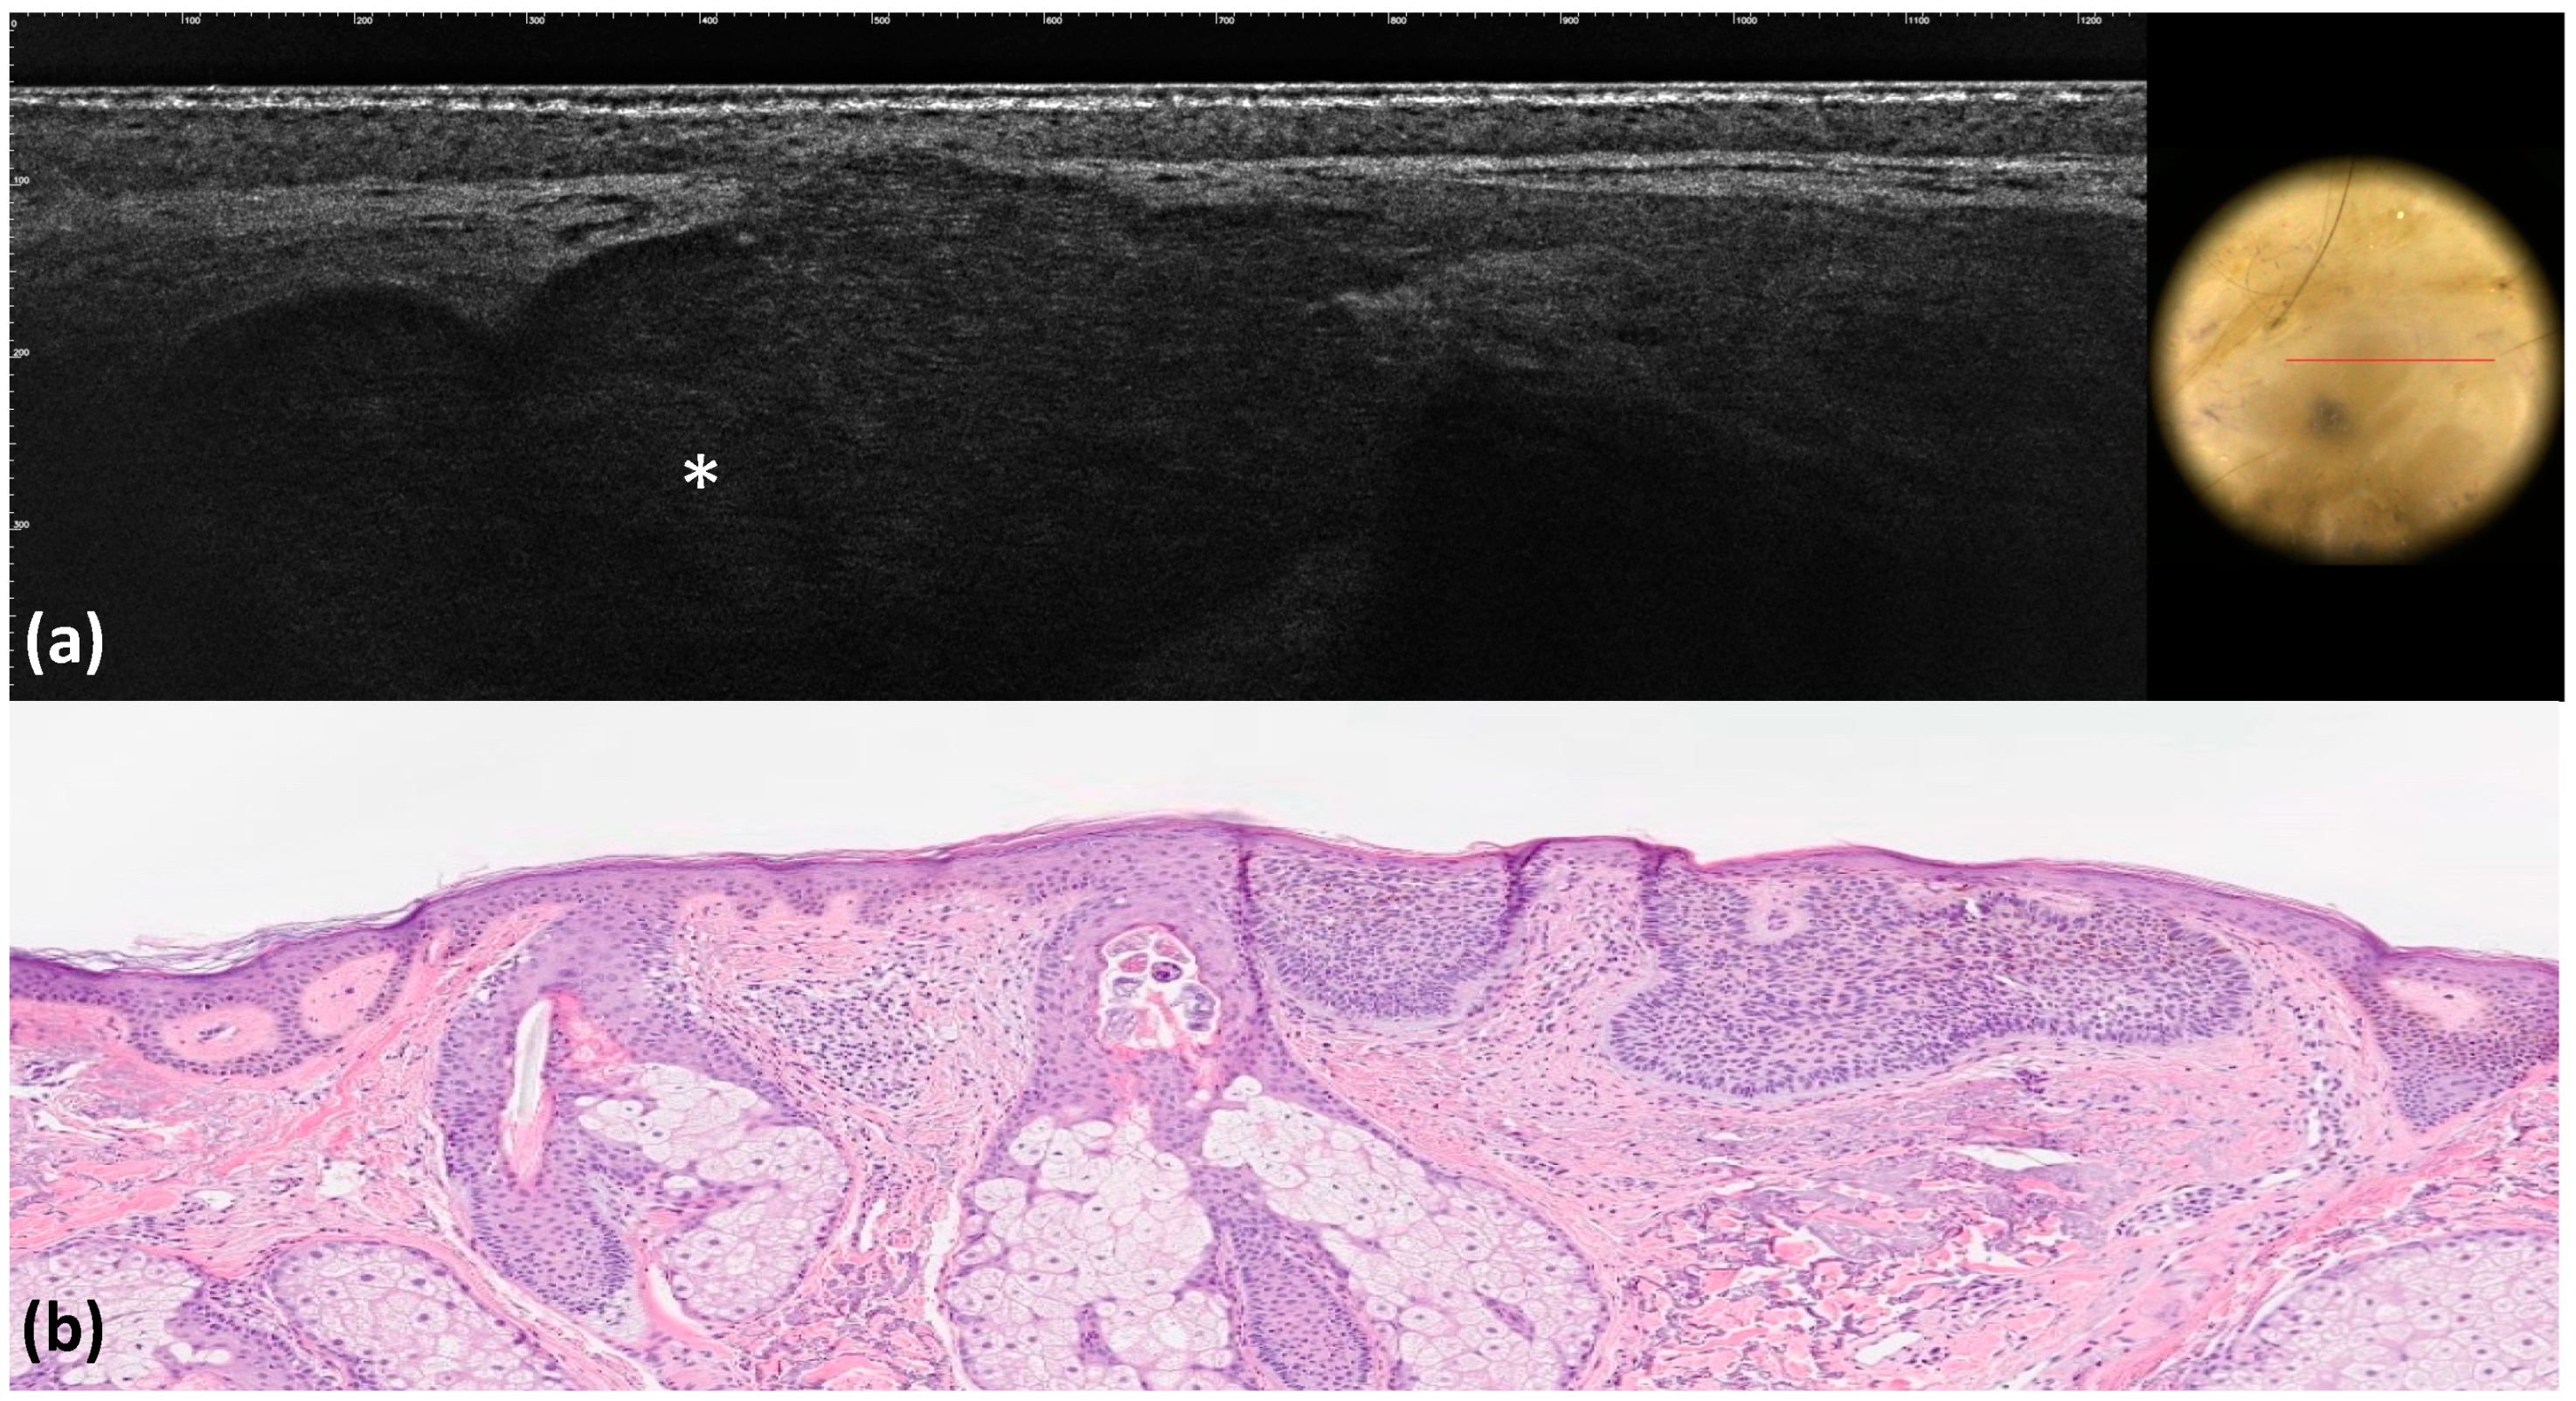

- Palmisano, G.; Orte Cano, C.; Fontaine, M.; Lenoir, C.; Cinotti, E.; Tognetti, L.; Rubegni, P.; Perez-Anker, J.; Puig, S.; Malvehy, J.; et al. Dermoscopic criteria explained by LC-OCT: Negative maple leaf-like areas. J. Eur. Acad. Dermatol. Venereol. 2023, 38, e271–e273. [Google Scholar] [CrossRef] [PubMed]